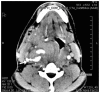

We present the case of a mixed martial arts (MMA) cage fighter who presented to the emergency department with a right sided common carotid artery pseudoaneurysm as a result of a neck trauma at an MMA event. We discuss the management of blunt force neck trauma, differential diagnosis, imaging findings and review the literature on blunt cerebrovascular injury following blunt force injury to the neck.